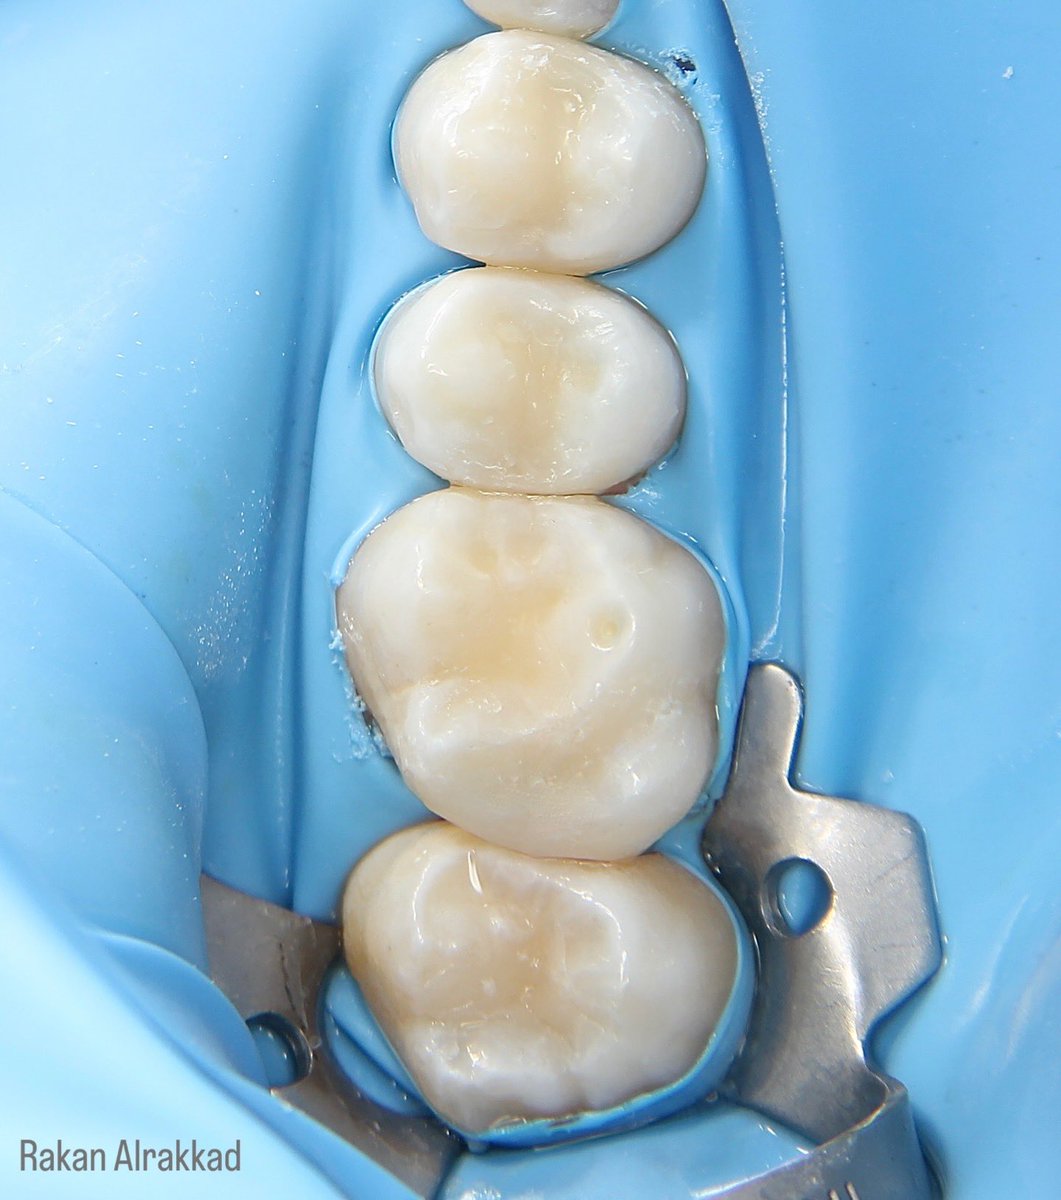

E-max Endocrown for #36 😍🤍 All procedure done under rubber dam IDS , surface treatments and cementation تلبسية جزئية من مادة الخزف للحفاظ على الضرس بعد علاج العصب 🦷

E-max Endocrown for #36 😍🤍

All procedure done under rubber dam

IDS , surface treatments and cementation

تلبسية جزئية من مادة الخزف للحفاظ على الضرس بعد علاج العصب 🦷